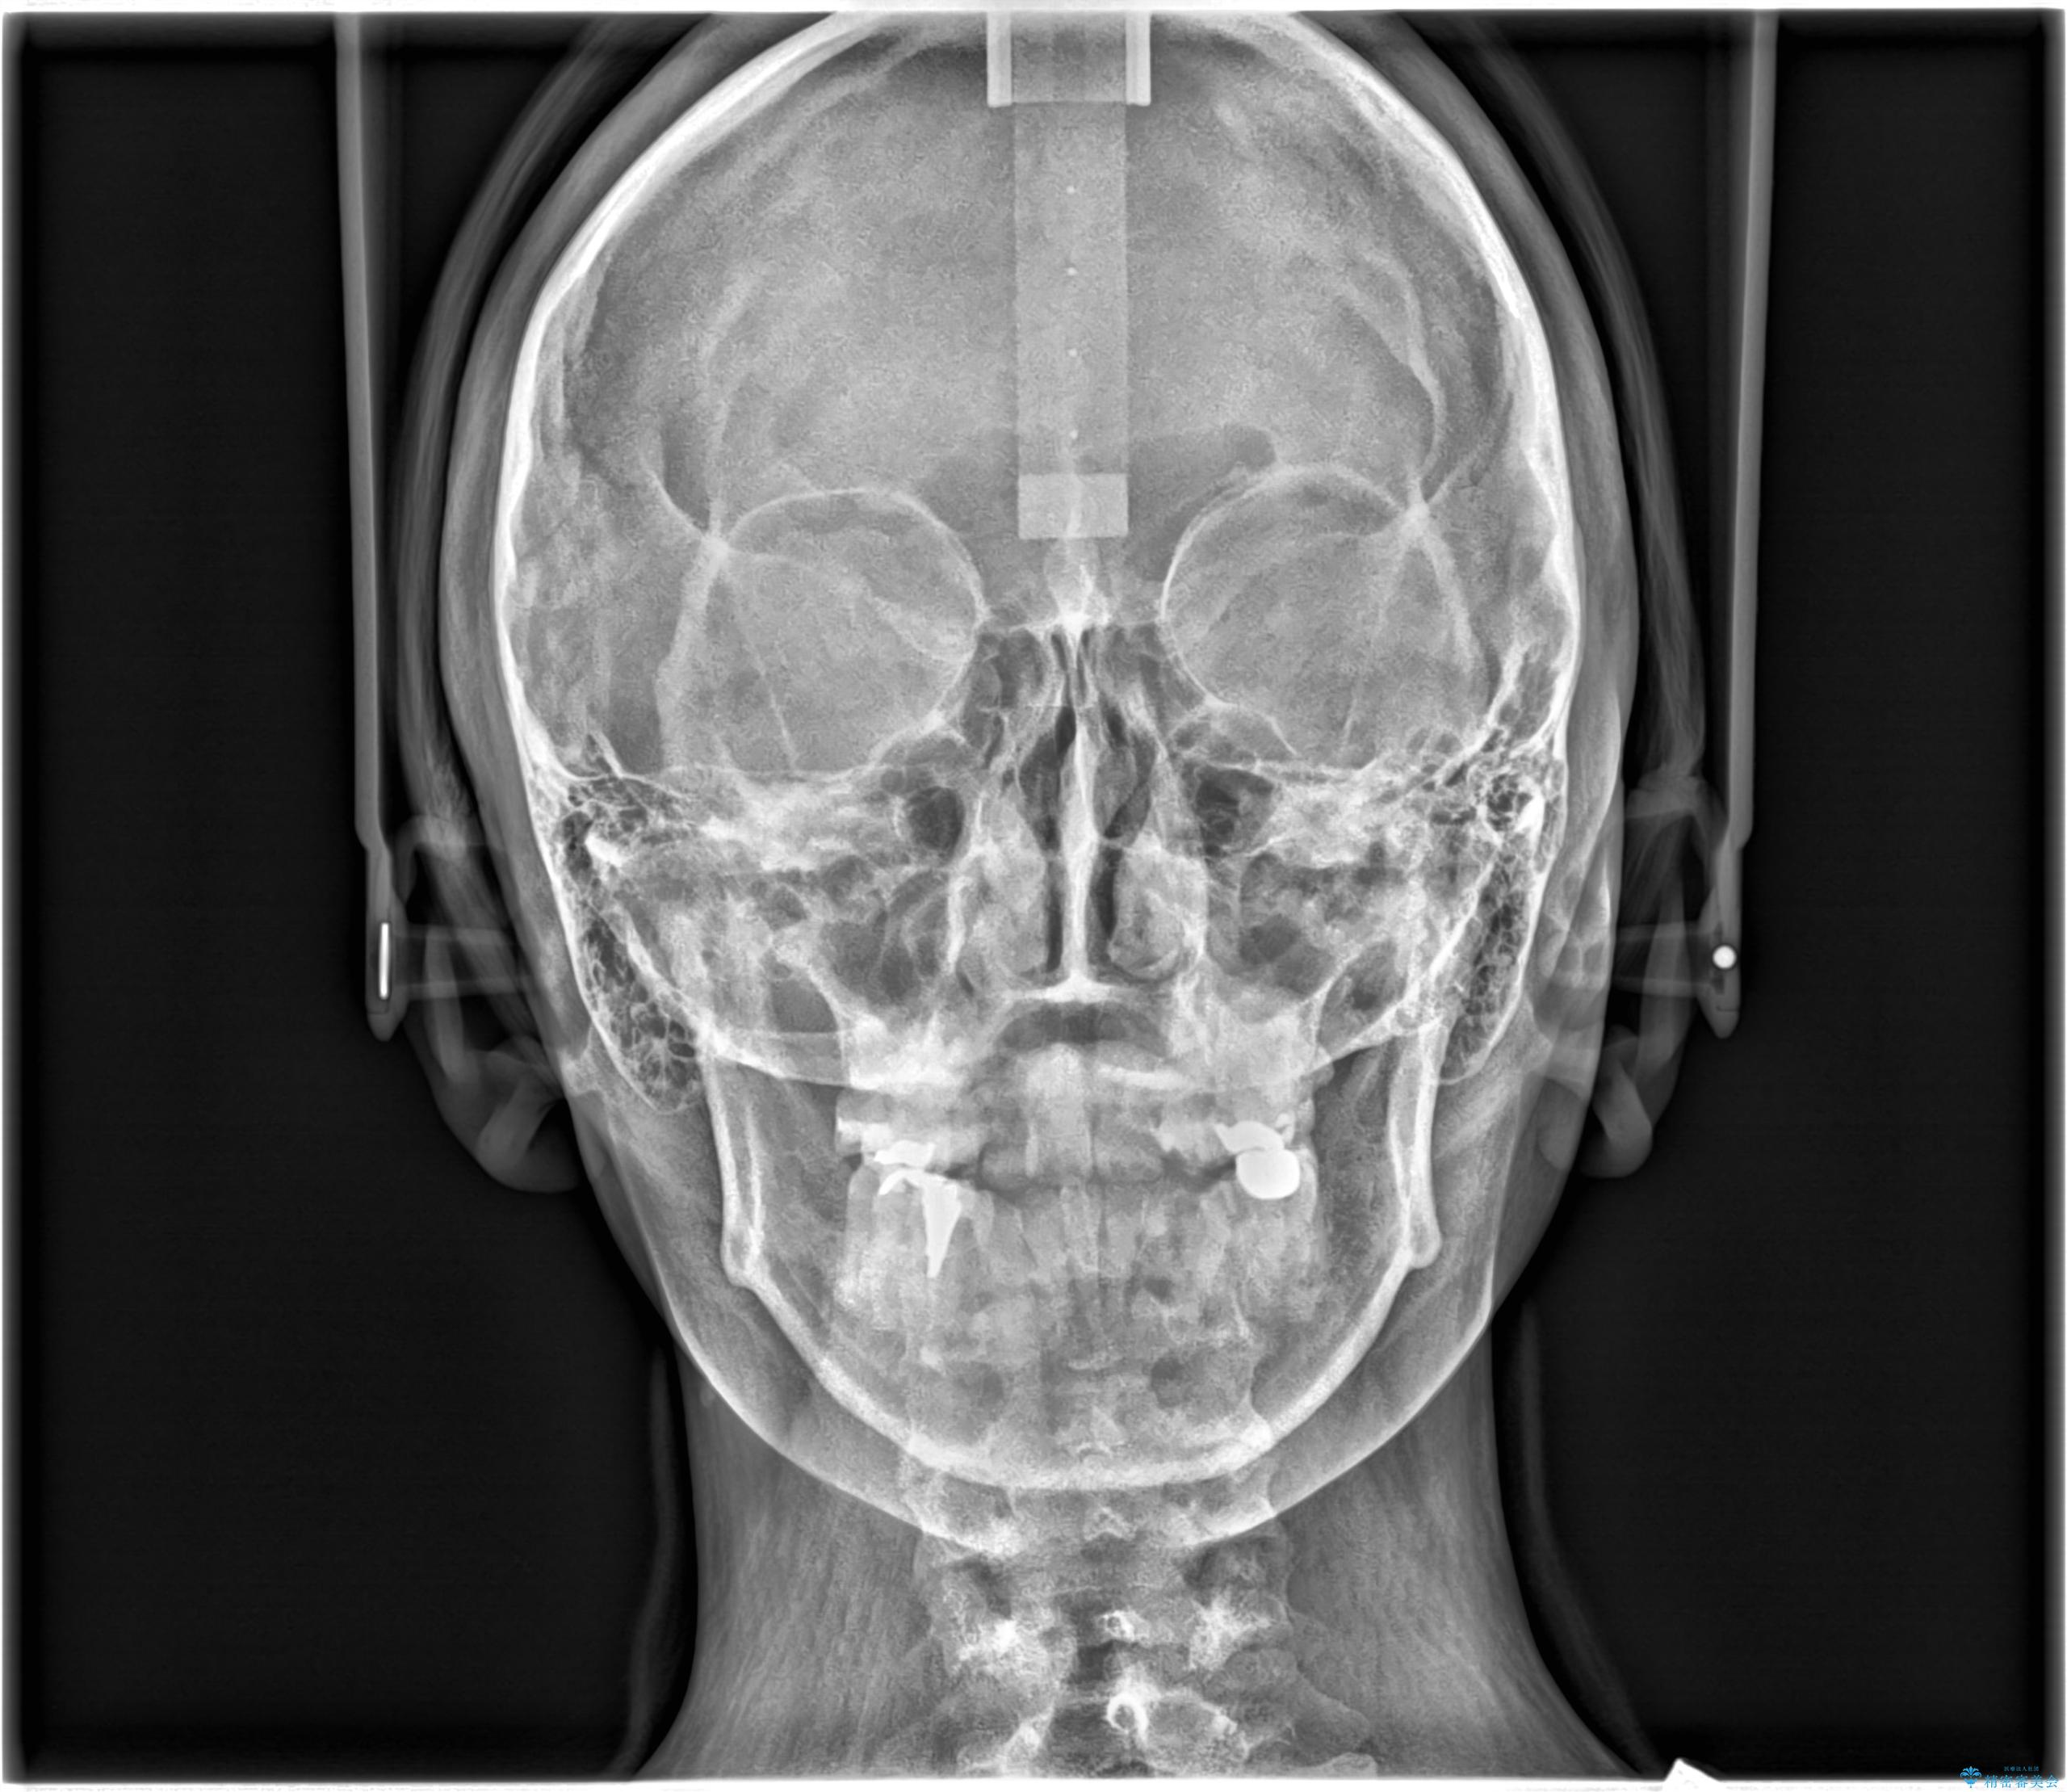

- 開咬と歯のデコボコ(叢生)、八重歯を主訴にご来院された患者様です。

矯正の精密検査の結果、上顎左右4番および下顎左右5番の計4本を抜歯し、ワイヤー矯正(クリア装置)にて治療を行いました。